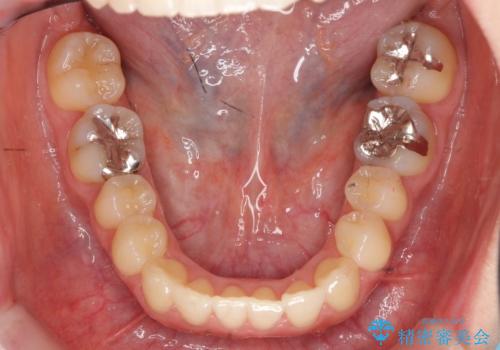

上の前歯が一部引っ込んでいる 下のがたがた マウスピース矯正

- 前歯2本が後ろに引っ込んでいる状態でした。

マウスピースで歯を抜かずに矯正しました。

かみしめがある方は、奥歯のかみ合わせが弱くなることがマウスピース矯正の欠点ですが、装着時間や時間帯を工夫して奥歯もしっかりかんだ状態で矯正終了をしています。